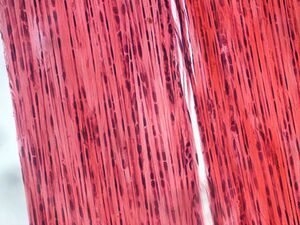

this contains more fiber and few cells than loose connective tissue الإنجليزية

image الإنجليزية

Dense connective tissue-400x.jpg

٢٬٠٤٨ × ١٬٥٣٦؛ ٢٫١٩ ميجابايت